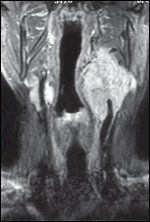

FIGURE 4

T2-Weighted MRI Study With Gadolinium Contrast

Although CT is the study of choice for the evaluation of bone involvement, magnetic resonance imaging (MRI) provides meticulous soft-tissue detail and defines skull-base, intracranial, dural, and neural involvement, especially with the use of gadolinium enhancement (Figure 4).[28] Augmented by its ability to produce images in multiple planes, MRI is superior to CT in defining the relationship of paragangliomas to adjacent vascular and skull-base structures.

MRI studies of paragangliomas demonstrate a background tumor matrix of intermediate signal intensity on T1-and proton density-weighted images and moderately high signal intensity on T2-weighted images, along with scattered areas of focal signal voids, reflecting high-flow blood vessels.[44] Intense homogeneous contrast enhancement is seen.[44] On T2-weighted images, the classic MRI "salt and pepper" appearance, originally described by Olsen et al[45] and present in most lesions greater than 1.5 cm, reflects signal voids intermixed with regions of focally high signal intensity, the latter of which are probably due to sites of slow flow within the image plane (Figure 4).[44]

These findings, however, are not specific for paragangliomas, and may be seen with other hypervascular lesions (eg, metastasic renal cell carcinoma and thyroid carcinoma). That said, the typically smooth contour, sig- nal characteristics, and location of paragangliomas, coupled with a detailed clinical history and physical findings should result in an accurate diagnosis.